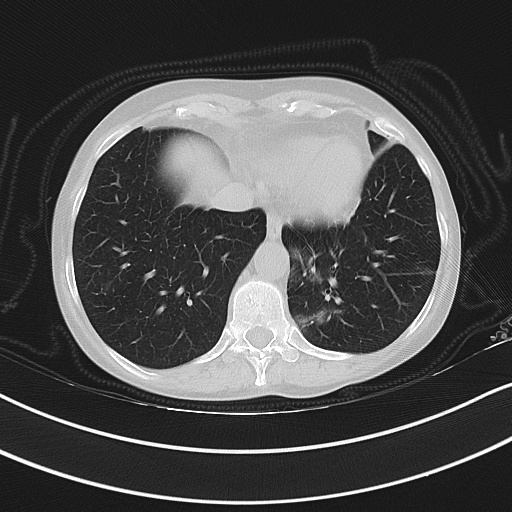

Figure 3 illustrates this further. It presents three cases of unsegmented slices of a CT scan (left column), along with their cases when they are segmented with conventional approaches (middle column) and with our proposed framework SAM2CLIP2SAM (right column). It is evident that the segmentation result with our approach is more accurate and error-prune. In the first case (top row), the mediastinal mass between the left and right lungs is kept when the slices are segmented with conventional approaches, whereas it is not kept (i.e., it is black) when the slices are segmented with our SAM2CLIP2SAM framework. In all cases, one can also note that a bit of the pleural space (e.g. on the peripheral of the lungs) is also kept and is not masked when the slices are segmented with conventional approaches; this is not the case when the slices are segmented with our SAM2CLIP2SAM framework.

Original-Unsegmented Conventionally segmented SAM2CLIP2SAM segmented